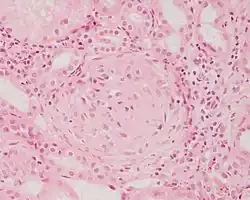

![]() |

Meningoma | Concentrically calcified basophilic structure in the centre of the field in a meningioma. | Category: Histopathology of meningoma | meningoma |